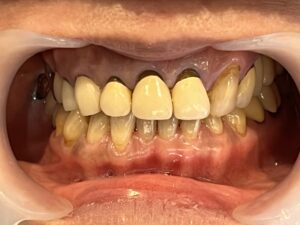

メンテナンスでいつもお越しいただいている長年の患者様が、

「前歯をもう少し綺麗になおしたい」「歯茎との境が黒くなっているのが気になる」とのことで、

仕事や生活の都合上、タイミングがあったので今回審美治療をスタートすることにしました!

元々、上の前歯に入っている補綴物の状態がこちらです。

歯と歯茎の境が黒くなっているのがわかります。

まずは元々入っている補綴物を外し、仮の歯を入れていきます。

仮歯を入れた状態がこちらです。

歯科治療において、仮歯の役割はとても重要になります。

嚙み合わせの状態や、審美的な見た目など、

仮歯の段階で何かしらのエラーに気づくことができれば事前に修正することができます。

歯肉が安定してきたら、最終の補綴物を入れる前に

天然の歯にホワイトニングをかけていきました。

白くなった歯に合わせて最終の補綴物を入れていきます。

そして前歯にフルジルコニアセラミッククラウンを入れた状態がこちらです。

Before After

歯と歯茎の境もなくしっかりとフィットし、綺麗な仕上がりになりました。

笑顔もとても素敵ですね♪

患者さまにも満足していただけてこちらも嬉しく思います。